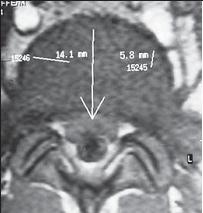

На МРТ № 11 наблюдается парамедианная грыжа межпозвонкового диска, которая как бы обхватывает с двух сторон спинной мозг На МРТ № 12 наблюдается медианная (срединная) грыжа межпозвонкового диска, которая часто протекает безсимптомно и может достигать больших размеров МРТ № 13 ![]() МРТ № 14